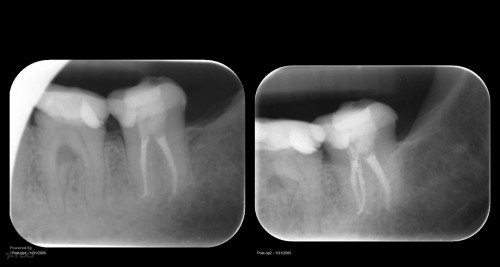

Disappointing recall

Busy recalling cases from the 10-15 yr time frame. Had I just done 5 yr recall, I’d never know …. gbc